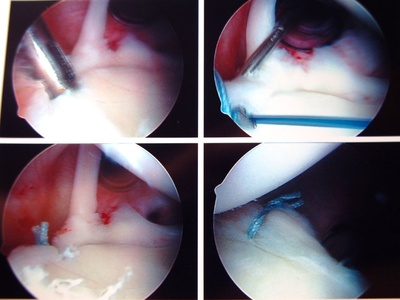

| Arthroscopy (Knee/Shoulder) | Orthopedic Surgery | Diagnose/Repair | Endoscopic |

Arthroscopy (Knee/Shoulder)

Minimally invasive joint surgery using a camera and small instruments to treat meniscal tears, ACL injuries, and more.

| Anterior Cruciate Ligament (ACL) Reconstruction | Orthopedic Surgery | Reconstruct | Arthroscopic |

Anterior Cruciate Ligament (ACL) Reconstruction

Reconstruction of a torn ACL using a graft to restore knee stability, common in sports injuries.